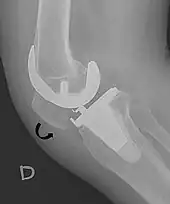

Patella baja[4]

A patella baja is a low-riding patella. A long-standing patella baja may result in extensor dysfunction.[5]

Insall-Salvati ratio (A divided by B).[6]

The Insall-Salvati ratio helps to indicate patella baja on lateral X-rays, and is calculated as the patellar tendon length divided by the patellar bone length. An Insall-Salvati ratio of < 0.8 indicates patella baja.[6]